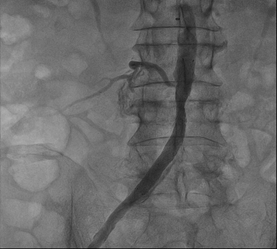

Trước nguy cơ cắt cụt chi nếu không tái thông mạch máu nuôi dưỡng mà trực tiếp là động mạch chậu chung; bệnh nhân N.T. được ekip các bác sĩ tiến hành can thiệp đặt stent động mạch chậu chi dưới qua da bằng ống thông động mạch. Ca can thiệp được thực hiện thành công ngoài mong đợi.

Sau khi đặt Sten |